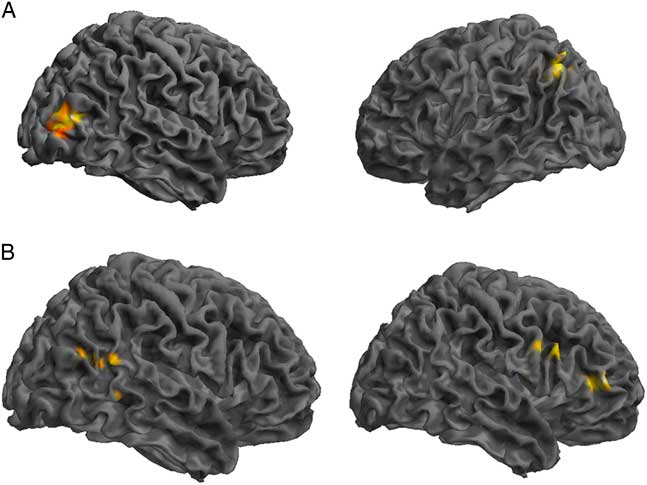

GICA Results: Control Group Compared to SRC Group

Comparing the DMN components between the control and SRC groups at time 1 revealed reduced functional connectivity in the SRC group compared to the control group (control>SRC) in the right inferior frontal gyrus (IFG), middle frontal gyrus (MFG), middle temporal gyrus (MTG), and posterior cingulate. Hyperconnectivity in the SRC group (SRC<control) was predominately seen in posterior regions, including left cerebellum and precuneus, and right middle occipital gyrus (MOG). No differences were found between the control and SRC groups at time 2 (Table 2; Figure 1).

Fig. 1 Significant differences in rs-fMRI functional connectivity between the SRC group and the control group at time 1. (A) Greater connectivity and (B) reduced connectivity in the SRC group compared to the control group. (A) Shown: right MOG and left precuneus; Not shown: left cerebellum. (B) Shown: right IFG, MFG, MTG, posterior cingulate.

Table 2 Differences at time 1 between the control group and the SRC group within the DMN component derived using GICA, in which greater functional connectivity in the SRC group is indicated by SRC>Control, and reduced functional connectivity in the SRC group is indicated by SRC<Control

L=left hemisphere; R=right hemisphere; BA=Brodmann area; MOG=middle occipital gyrus; IFG=inferior frontal gyrus; MFG=middle frontal gyrus; MTG=middle temporal gyrus.